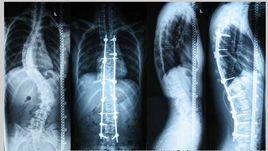

3.青少年特發性脊椎側凸側:本症發生與青少年,發病時沒有胸背通,是進行性的側凸,一般因肩胛高低不對稱才發現。其側凸多發生在胸3以下胸11以上,波及8~10個椎體。

治癒:症狀體徵消失,X線片示側凸恢復5°以下者。

好轉:胸背痛減輕,X線片示側凸有改善,但未到5°以下。

無效:症狀體徵和X線片示五改變。